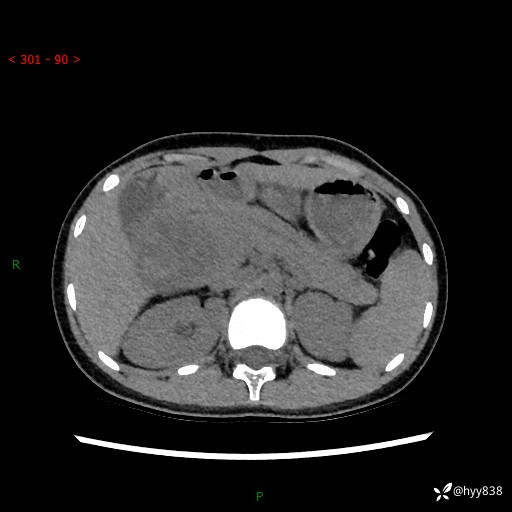

病例小姑娘,超声提示上腹部巨大包块。平扫就能轻松搞定的病变--结果公布

性别:女

年龄:13岁

简要病史:超声提示上腹部巨大包块

上腹部CT平扫

胰腺实性假乳头状瘤 (17)